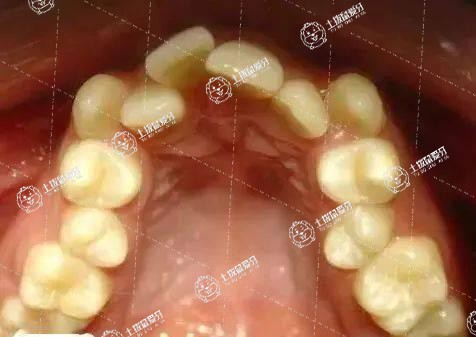

不拔牙矯正也不是所有患者都會變齙牙,比如患者是有牙列擁擠,需要矯正不齊的牙齒,但是患者牙弓是比較窄的,所以這個時候我們是可以通過擴弓的方法將牙弓擴大,牙弓擴大之后就會提供一定的間隙,這個時候再將牙齒排齊就不會變齙牙。

如果患者已經過了生長發(fā)育高峰期,牙弓不能夠再擴大或者是牙弓已經很大,不能夠再擴的時候,這個時候牙列擁擠沒有拔牙矯正就會變成齙牙。

牙齒擁擠不拔牙矯正一般會凸出來。如果有嚴重的牙列不齊,牙列擁擠,但沒有進行拔牙矯正,矯正后可能變成齙牙,這主要是牙齒擁擠嚴重,如果沒有足夠的間隙,就需要通過擴弓和傾斜牙齒的唇來對齊牙齒。經過這種矯正后,牙齒就變成了齙牙。建議患者積極去醫(yī)院進行檢查和治療,多喝一些溫水。